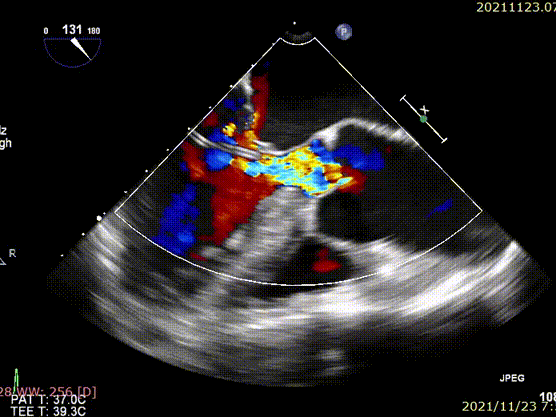

术前超声

术后超声

心脏彩超:重度PNAR(三叶瓣),轻度MR,中度TR,左室舒张末内径53mm,左室收缩末内径35mm,左室射血分数(LVEF)为62%。

术后患者状态良好,CT评估未见异常,无瓣周漏,血流动力学良好。瓣膜植入后峰值流速0.82m/s,平均跨瓣压差1mmHg。